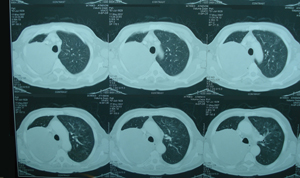

Εικόνα 2

Αξονική τομογραφία θώρακος που δείχνει την θέση του όγκου. Πρόκειται για μάζα εκ μαλακών μορίων, με ομαλά όρια και ομοιογενή πυκνότητα.